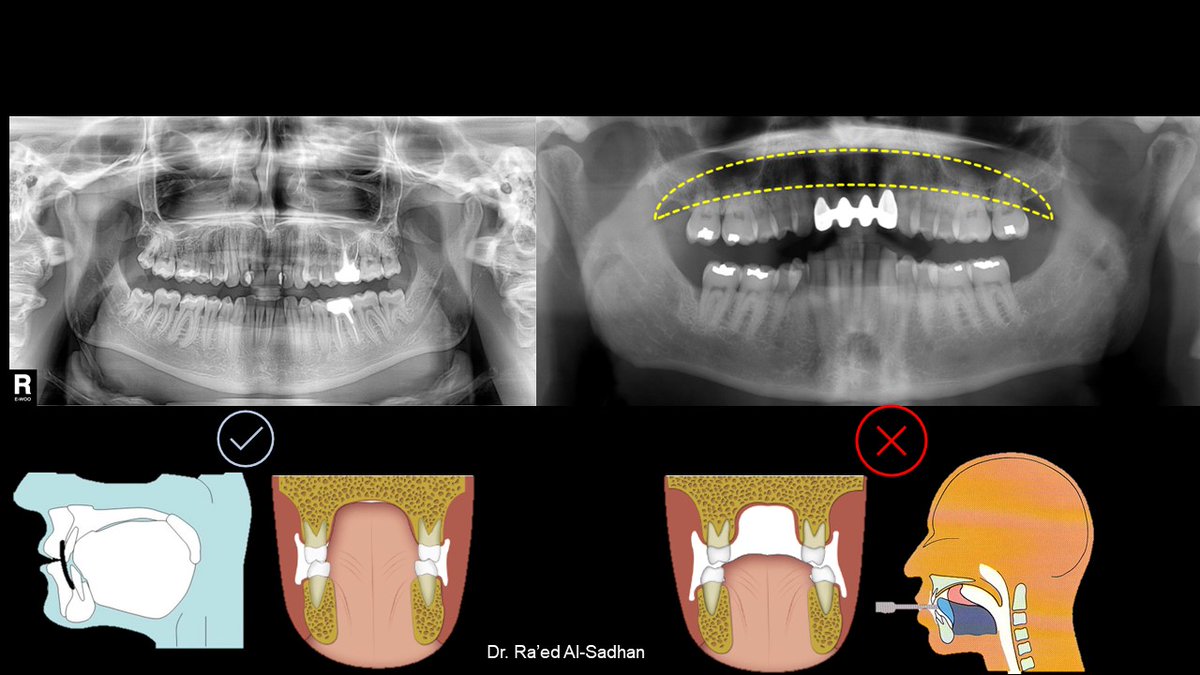

الوضع الصحيح للرأس أثناء التصوير البانورامي يضبط فيه طرف الخط الضوئي الأفقي مع محور فرانكفورت Frankfort plain على أعلى فتحة الأذن (upper margin of ear canal (porion ثم رفع أو إنزال ذقن المريض حتى يلامس الطرف الآخر لخط الضوء أسفل محجر العين inferior margin of orbit (orbitale)

وعندما يوضع الرأس في هذا المستوى وتعض أطراف الثنايا على الثلمة التي في العود الذي في جهاز الأشعة incisal pin تكون الأسنان في وسط طبقة التصوير لجهاز الأشعة البانورامية وتظهر صورتها واضحة دون تشوه.

بينما إذا كان الذقن مرتفعا إلى الأعلى أكثر من اللازم تخرج الأسنان الأمامية من طبقة التصوير لجهاز الأشعة البانورامية وتظهر صورتها مشوهة ولاترى بوضوح.